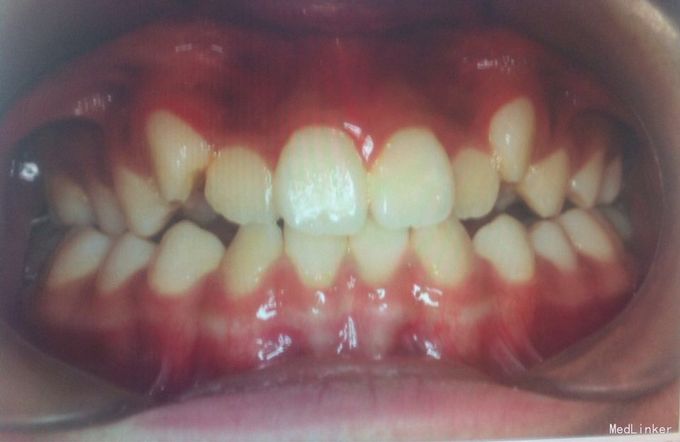

检查:恒牙期 右侧磨牙远中关系,左侧磨牙中性关系 前牙一度深覆合,正常覆盖 32、42未见 13、23唇侧错位 张口型异常 中线左偏约2mm 口腔卫生一般 X线未见32、42牙胚,28、38、48牙胚存在

诊断:安氏三类,先天缺牙 处理:拔牙矫治,直丝弓矫治器,拔除15、25,排齐整平上下牙列,关闭拔牙间隙,矫治后磨牙中性关系,前牙覆合覆盖正常,维持现有面型。